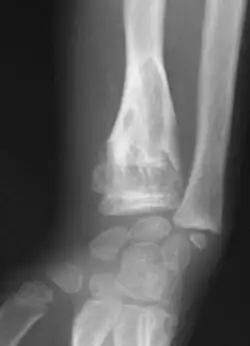

X-ray showing enchondromas localized in the lower part of the radius of a 37-year-old patient affected with Ollier disease -

Abnormal bone growth such as shortening or thickening and deformity may be observed in patients of Ollier disease. These bone lesions are visible at birth using radiography but are usually not screened or examined for until clinical manifestations present during early childhood. However, some patients may exhibit no signs of any symptoms.[1] One study found thirteen to be the mean age of diagnosis in patients with Ollier disease. In an X-ray, there would normally be the presence of several homogeneous lesions of an oval or elongated shape with bone edges that are slightly thickened.[3] With age, these lesions may calcify and appear as diffusely minute spots or stippled. Fan-like septations or streaks would be indicative of the presence of several enchondromas. Early detection and consistent and repeated monitoring is important in order to prevent and treat any potential bone neoplasms.